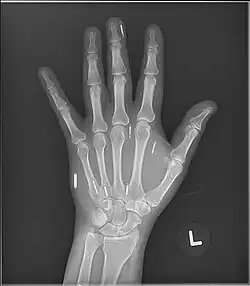

An X-ray of a biohacker's hand showing several implants.

Some chipped individuals have reported being turned away from MRIs due to the presence of magnets in their body.[77] No conclusive investigation has been done on the risks of each type of implant near MRIs, other than anecdotal reports ranging from no problems, requiring hand shielding before proximity, to being denied the MRI.

Other medical imaging technologies like X-ray and CT scanners do not pose a similar risk. Rather, X-rays can be used to locate implants.